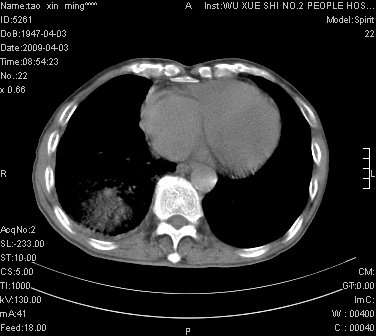

男.62.咯血.胸痛

是不是外伤的,看起来右侧肋骨骨折,右肺唑伤,右胸腔积血, 右肺背段可见一软组织肿块,边缘清晰,可以和中中央型肺ca合并

右下周围型肺癌,右侧胸腔积。

右下周围型肺癌,右下肺出血,右侧胸腔积。

1)考虑右肺下叶周围型肺癌,并右肺下叶肺出血。2)右侧少量胸腔积液。

1)考虑右肺下叶周围型肺癌。2)右侧少量胸腔积液。

右下肺阴影,右胸腔少量积液。